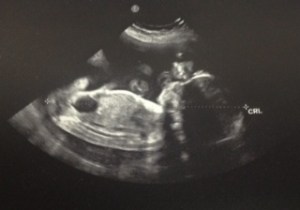

Everything at the beginning went smoothly. Our early ultrasound looked good. We heard the heartbeat. I felt really good– I was tired and wanted to eat… all the time… but never felt sick. Joe and I started dreaming and wondering if we’d have a boy or girl.

Because of my age, it was recommended we see a genetic counselor and were offered an additional screening ultrasound and testing. We decided to go ahead with the ultrasound because in my mind I thought it was screening for Down Syndrome and we figured we’d want to be prepared and possibly deliver somewhere in St. Louis versus in Illinois. You meet with a counselor first and they go through all the chances something will be found. And they are small. We went to the ultrasound room and that’s when our lives would change forever. The tech found a cystic hygroma on the baby. Basically excess fluid under the neck. It is an indication that something else is wrong– a chromosome or heart defect. We held out hope that it would go away or was caused by something so microscopic that you’d never know. With this information, though, we decided to go ahead with the DNA testing. They drew my blood which has the baby’s dna in it. And we waited two long weeks for results. They were inconclusive, meaning we were tested too early and had to wait and do it again.

In the meantime, we continued to have hope and also prepared ourselves for the possibility of Down Syndrome, Turners or a heart condition. We thought we could live with all of these. They’d present their own challenges but we would all get through. We had ultrasounds every two weeks. On the 16 week ultrasound, we were told the baby “looked good” and was most likely a girl but they’d confirm in two more weeks with the dna test and another ultrasound. But she was developing and growing and squirming around. It was beautiful.

We went to our 18 week appointment expecting to get the results of the dna. They were not back yet again. We’d have to wait 2 more days. The ultrasound started out really well. They confirmed it was a girl. Her brain, spine, heart, kidneys all looked good. The hygroma had gone away. We were so relieved. Then they found she had a club foot (meaning it is turned the wrong way). So along with the cystic hygroma and her small size the doctor told us she was concerned that our baby had Trisomy 18. And I felt like I got hit by a truck. Joe left with a positive hopeful outlook. I did not. And then we waited until Thursday for the call with the test results.

The most important news first: Zoey’s heart is still beating and she’s still squirming around. In fact, the ultrasound tech and doctor have a somewhat hard time getting the pictures they want because she won’t hold still. They also confirmed that even if something would happen at any point now, I’d still be able to hold her after delivery and that was comforting. It is important to me to get to see her, hold her.

We had another appointment yesterday with an ultrasound. One of the many strange parts of this journey is that we have a new status for how appointments go: awful or not awful. Yesterday was not awful so we consider that a win! Zoey’s heartbeat is still going strong and she was quite active yesterday. She also didn’t really want her picture taken. They got one of her profile and then she rolled over and refused to let us see her face. She’s tipping the scale at a little over one pound. There’s some extra fluid, but nothing to panic about yet. They did mention that if there is too much fluid they can sometimes drain it and I certainly did not ask for details on how that actually happens. There are some things I just don’t want to know. Just praying that it doesn’t get to that point! Often times the extra fluid is an indication that she’s not swallowing. There’s just so much that we don’t know until after birth. They can only tell so much from the ultrasound. The doctor was great and basically said let’s just try to get her at least 14 more weeks (they certainly don’t want her coming early—she’ll already have enough issues that adding those extra complications will not help anything). He also encouraged us just to focus on that: get her here. If she gets to go home with us we can buy anything we need later. Someone can always make a run to Babies R Us.

We had another appointment at Cardinal Glennon yesterday. I know I said last time that we’ve started considering appointments either awful or not awful, but as it turns out they can be both. First, her vital stats: Zoey’s heart is beating well and she now weighs in at about 2 pounds. She’s comfortably settled in with both feet poking at my ribs. She’s very active and still likes to dramatically put her hand in front of her face for the ultrasounds. I mentioned that I don’t feel like I’d ever make the “kick counts” that so many people talk about and it seems odd because she’s obviously extremely active. I still have excess amniotic fluid which is giving her more room to float so that could be why I don’t feel her as often—although there are times I think she’s doing cartwheels and taking great pleasure in punching my bladder. I love those moments (even when they come in the middle of the night) and hope that she starts punching hard enough that Joe is able to feel her soon too.

After the long, exhausting meeting with the neonatologist, we had an ultrasound and were able to see Zoey squirming around. Again, it goes back to being both amazing and heartbreaking. She looked so real this time. We saw features we haven’t seen before. The ultrasound tech mentioned it looks like she has long toes—like mine. And it broke my heart wondering what other features she’ll have. My eyes? Joe’s coloring? And all you can wonder is “how?” How are we going to get through this? How did this happen to her? How is this diagnosis true when you can see her wiggling and flipping and hiding from the ultrasound tech? How are we going to say goodbye when it is time?

Yesterday we met with Dr. Vlastos, had another ultrasound and got set-up to deliver at St. Mary’s. Little Zoey is now weighing in at 3 pounds so still small, but growing. She was happy to show off her heart, kidneys and legs but she still puts her hand in front of her face so we don’t get to see her pretty little nose or eyes. I thought she was embarrassed, but Joe thinks she’s a drama queen. Her heart is still beating well and there are not currently any signs of pre-term labor. I’ll keep her with me as long as possible! As much as I want to hold her, I also want to keep her safe for as long as I can.

34 Weeks—and Zoey is 3lb8oz

Zoey passed her first “non-stress test” last week but I’m wondering if we will or need to continue doing them. I don’t feel like it will change the outcome of anything. What will be, will be. All the appointments are stressful and I wonder if our time is better served just loving her. I’ll be back at Cardinal Glennon Thursday, so I will try to think clearly and ask more questions. I thought she was pretty cute on the ultrasound last time though—she was tucking and untucking her legs. And of course hiding her face.